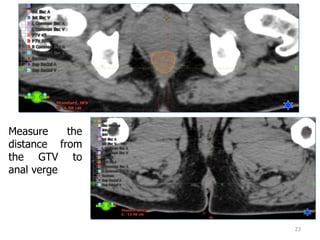

Lowest boundary of GTV

22

23

Measure the

distance from

the GTV to

anal verge

In the SAGITTAL view, use

the measuring tool to check

the vertical extent of the GTV

contour.